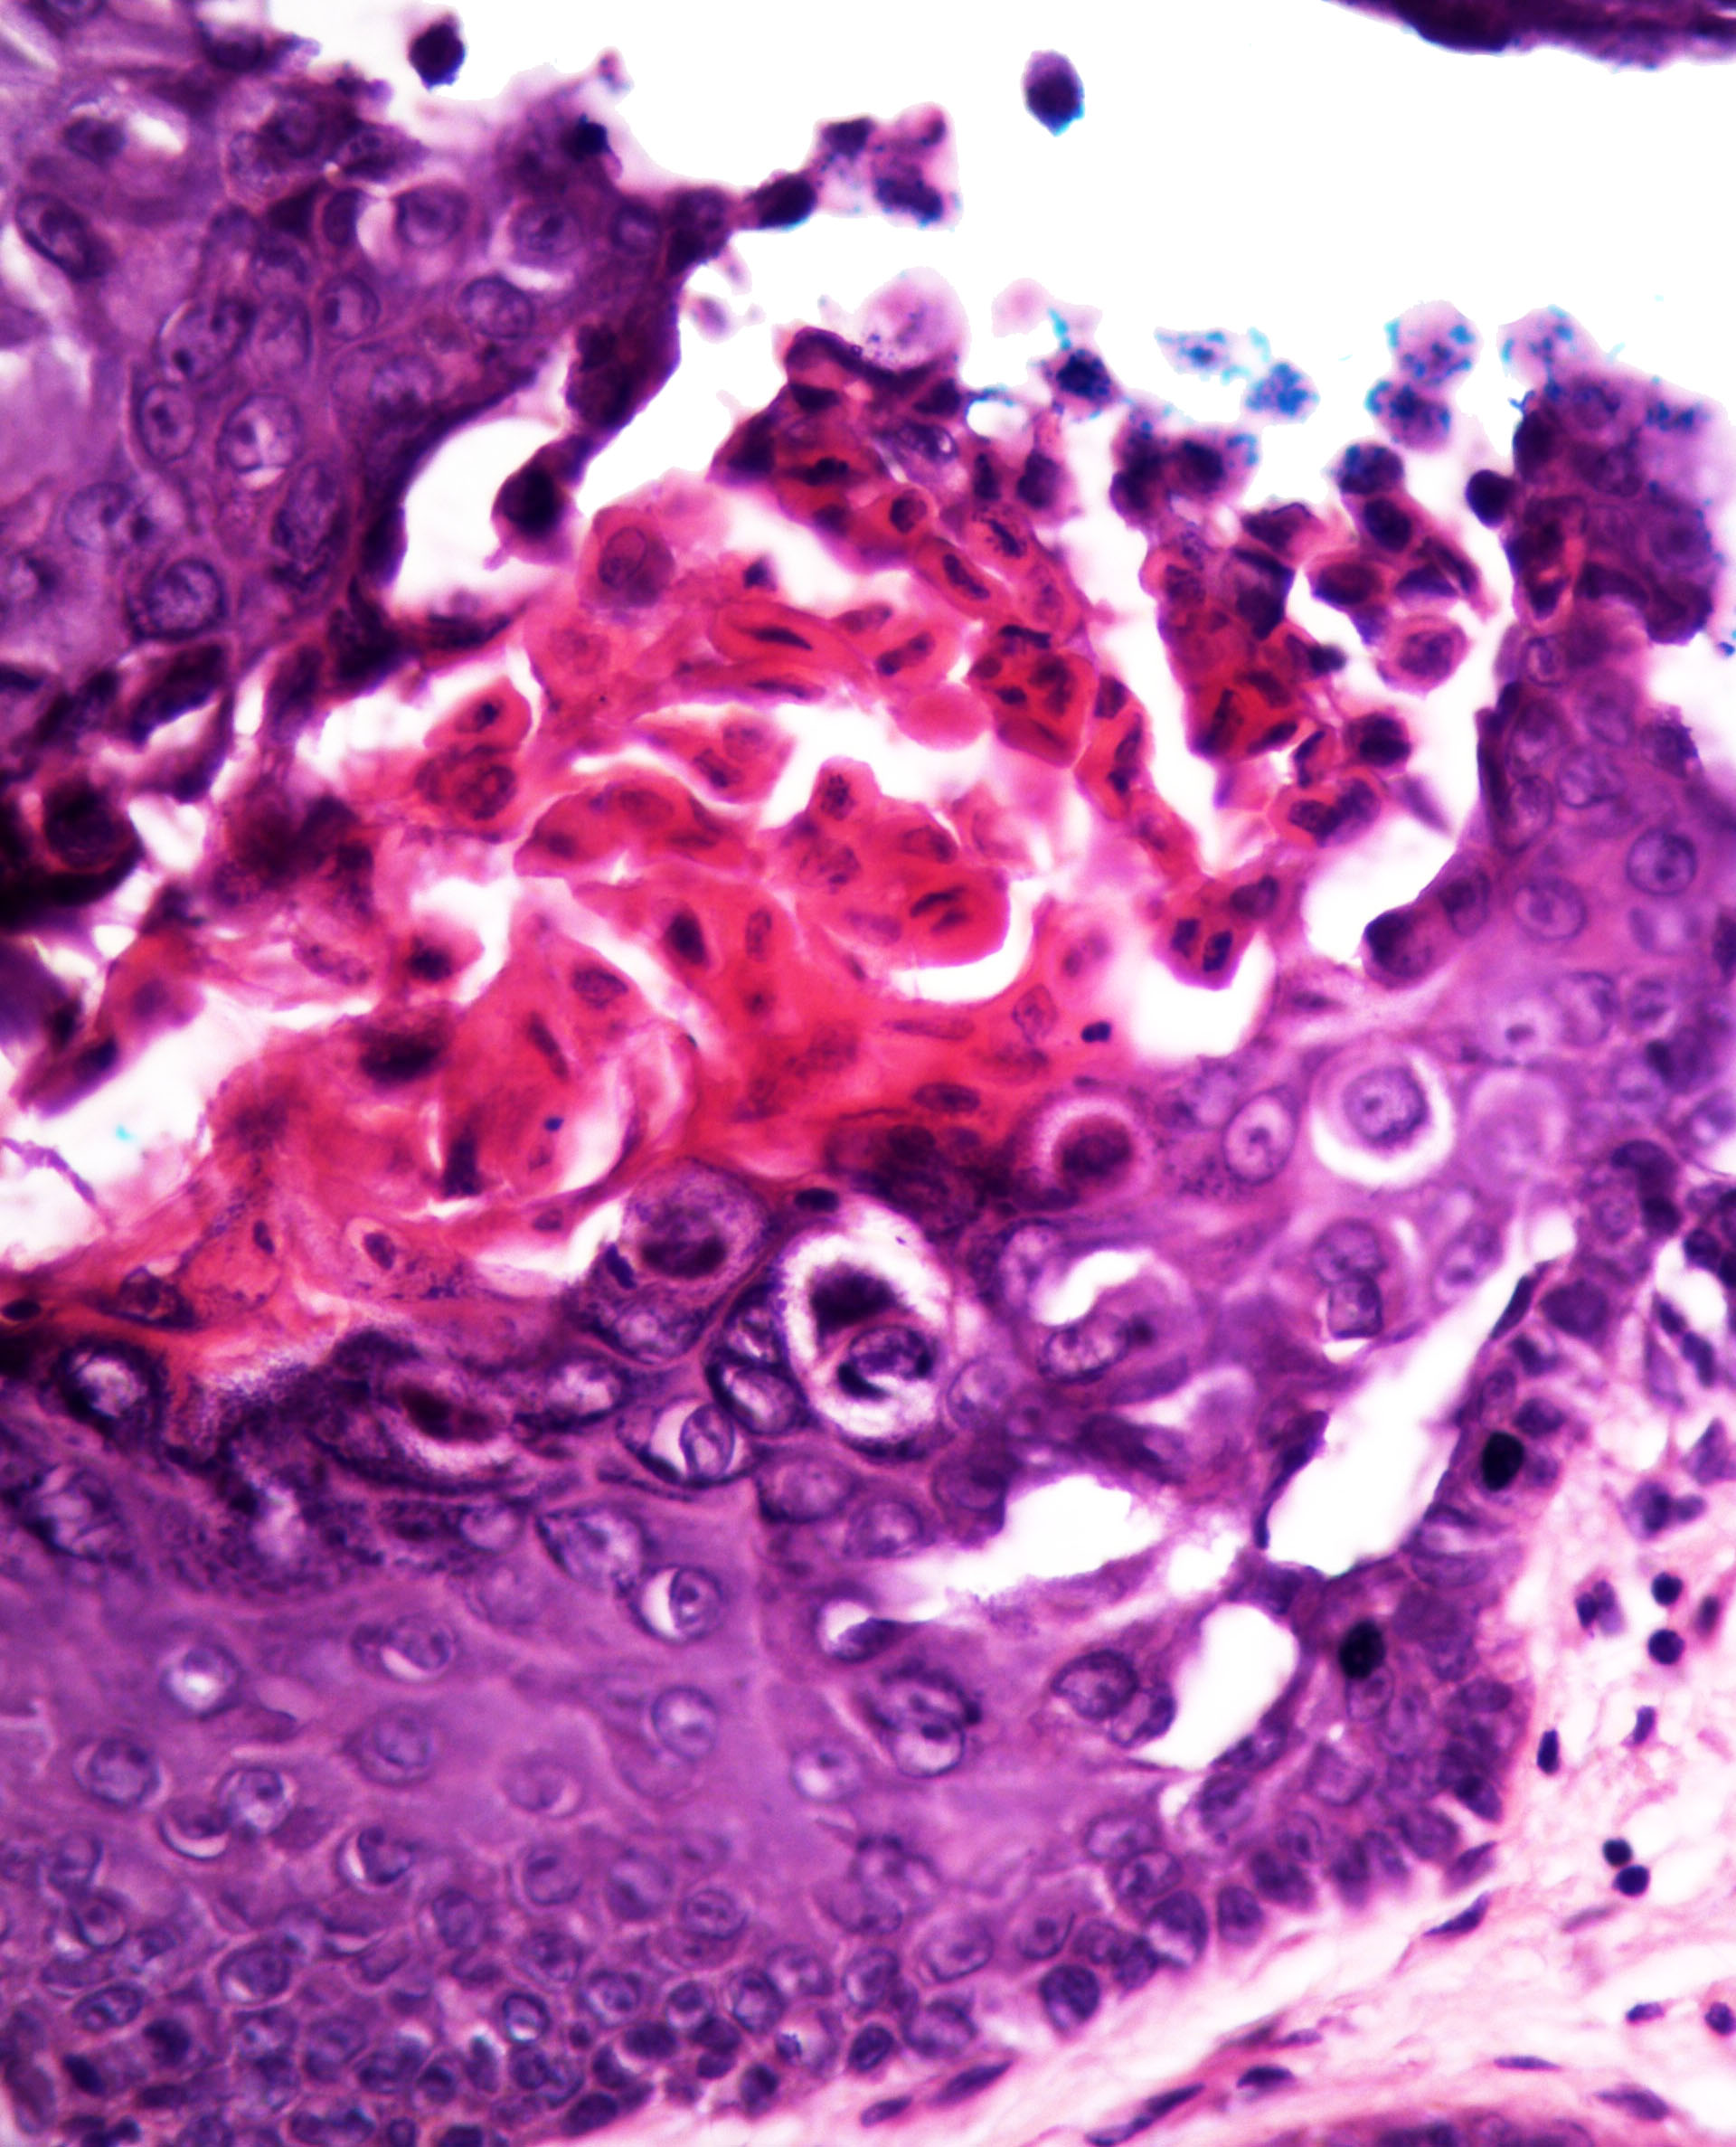

Microscopic (histologic) description

- Acantholysis with characteristic dyskeratosis forming corp ronds and grains

- Corp rond: rounded keratinocyte in superficial spiny and granular layer with basophilic / pyknotic nucleus, perinuclear halo and often a rim of eosinophilic cytoplasm (J Dermatol 2017;44:232)

- Grain: elongated keratinocyte in the stratum corneum with small basophilic nuclei and intensely pink cytoplasm; appears as plump parakeratosis; may form tiers (J Dermatol 2017;44:232)

- Suprabasal acantholysis and clefting with retained single layer of basal keratinocytes overlying dermal papillae which appear to project into the acantholytic cavity (villi) (J Dermatol 2016;43:275)

Microscopic (histologic) images